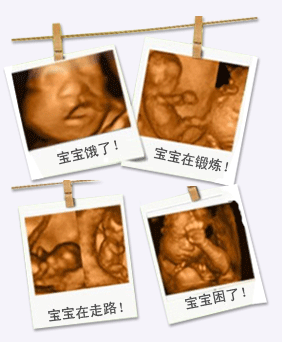

四維彩超拍攝胎兒在宮內(nèi)的圖片

此外,四維彩超能直觀、立體顯示胎兒的三維結(jié)構(gòu),實(shí)時(shí)地觀察孕婦宮內(nèi)胎兒的活動(dòng)圖像、生長(zhǎng)發(fā)育情況,為早期診斷胎兒先天性體表畸形和先天性心臟疾病提供準(zhǔn)確的科學(xué)依據(jù)。同時(shí)通過(guò)四維彩超觀察到的動(dòng)態(tài)圖像將可以成為胎兒的張高清寫(xiě)真集,準(zhǔn)媽媽的呵護(hù)從“零”開(kāi)始。推選閱讀 莆田哪里做四維彩超有優(yōu)惠